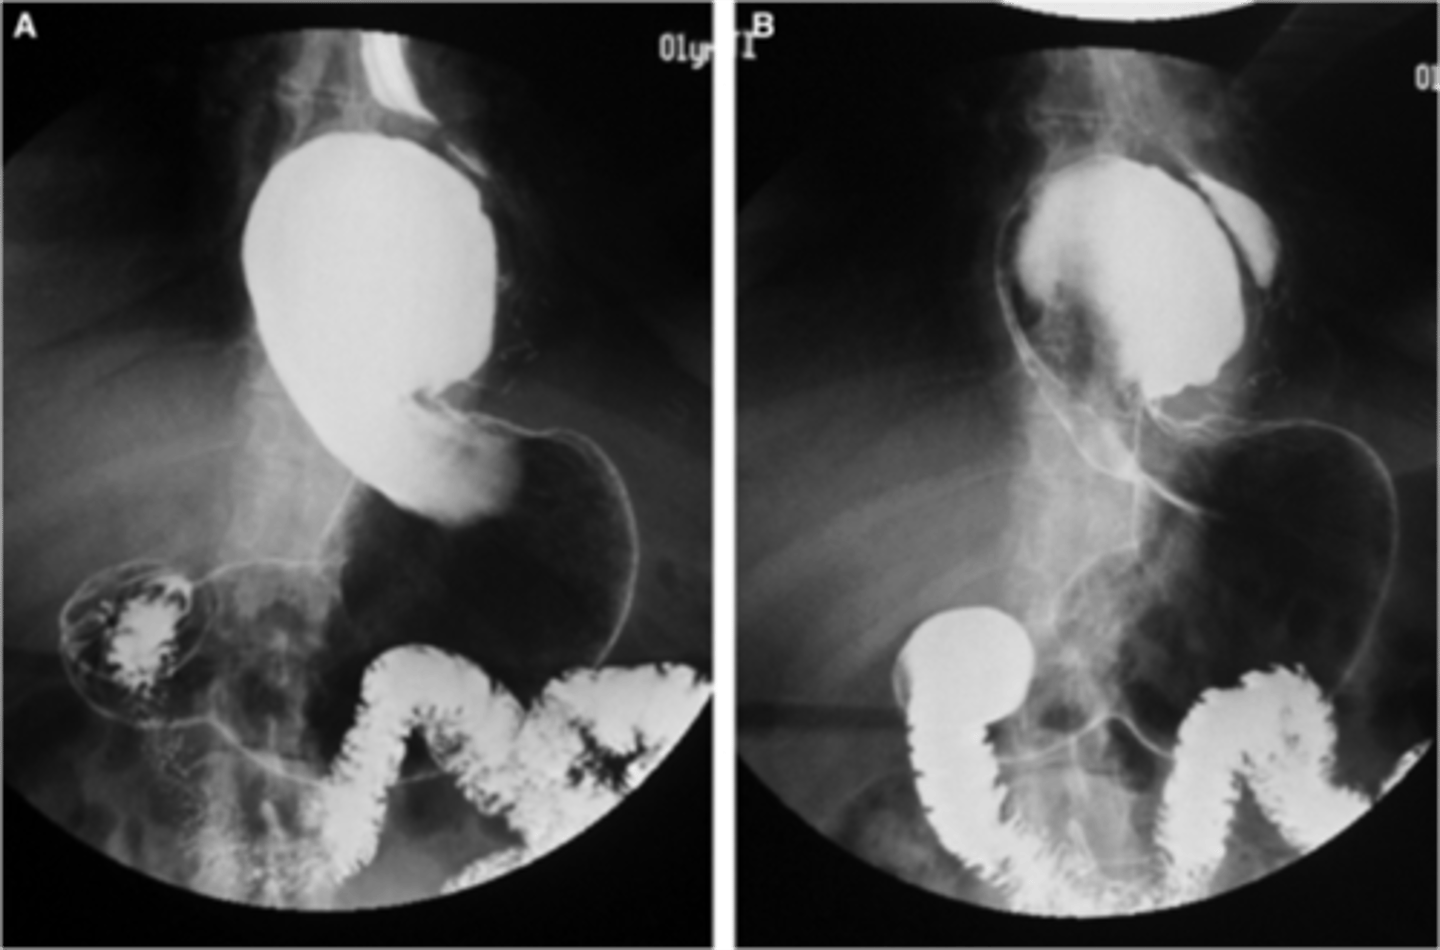

Normal barium swallow

Normal barium swallow (pic 2)